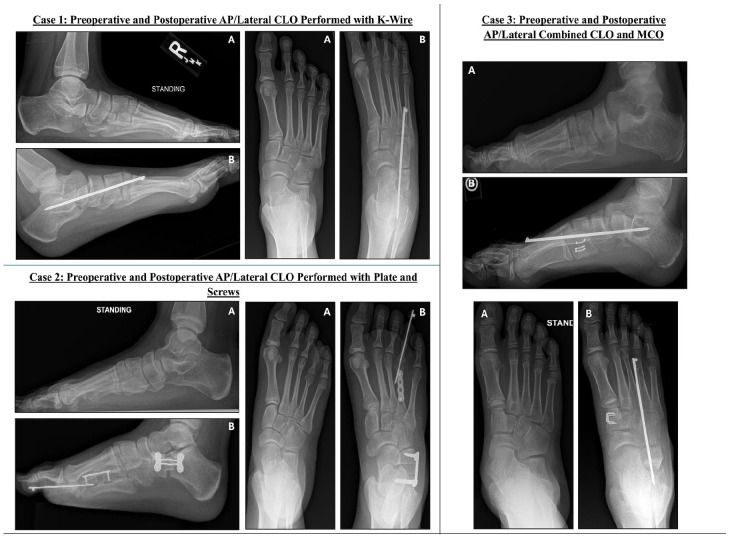

Methods: Children aged 8-18 who underwent CLO for painful FF correction were included. Retrospective chart review for PROMIS scores of pain and mobility were collected. Preoperative PROMIS scores were compared to PROMIS scores collected within 6-12 months postoperatively. Five PROMIS points was determined to be a minimal clinically significant difference, as this is half of the SD of the PROMIS metric. Preoperative and postoperative AP/lateral talo-first metatarsal angles were collected and compared. The patients with residual pain (PROMIS >55) after CLO were evaluated, and the effect of potential factors on residual postoperative pain was assessed.